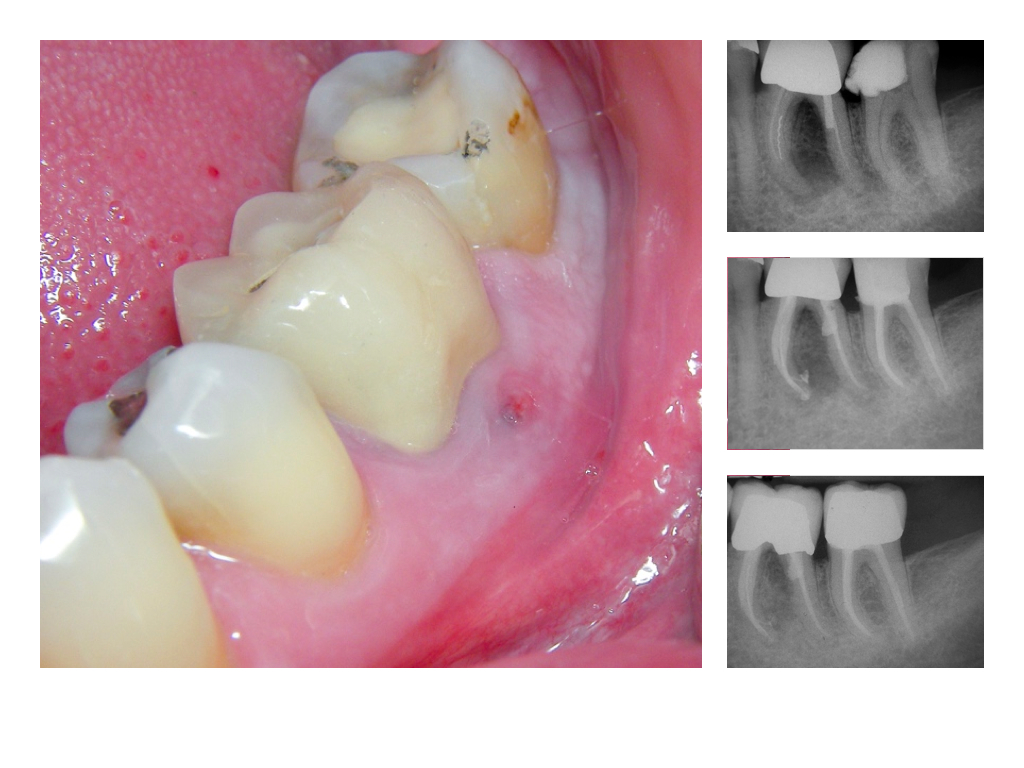

DMAWFR.008 Veröffentlicht 27. Februar 2012 am 1024 × 768 in Die Mutter aller WF – Revisionen – Recall nach 5,5 Jahren